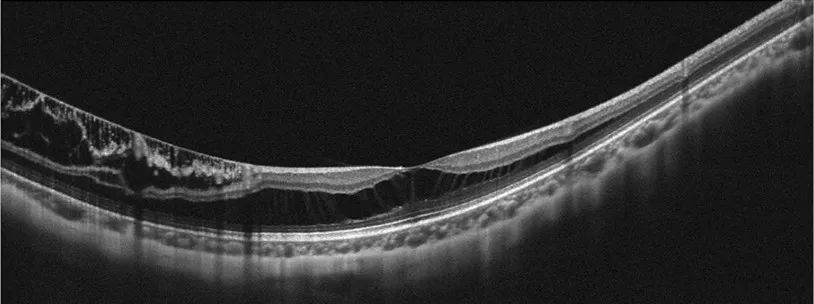

除了眼底照相,现在我们还可以进行相干光断层扫描(OCT)对眼底进行检查,这样可以获取比眼底彩照更精确的视网膜断层图像,可以更早的对疾病进行诊断,特别是各种类型的黄斑病变,如黄斑裂孔、黄斑前膜、黄斑水肿等,OCT可以让各种病变无处遁形。

高度近视黄斑劈裂